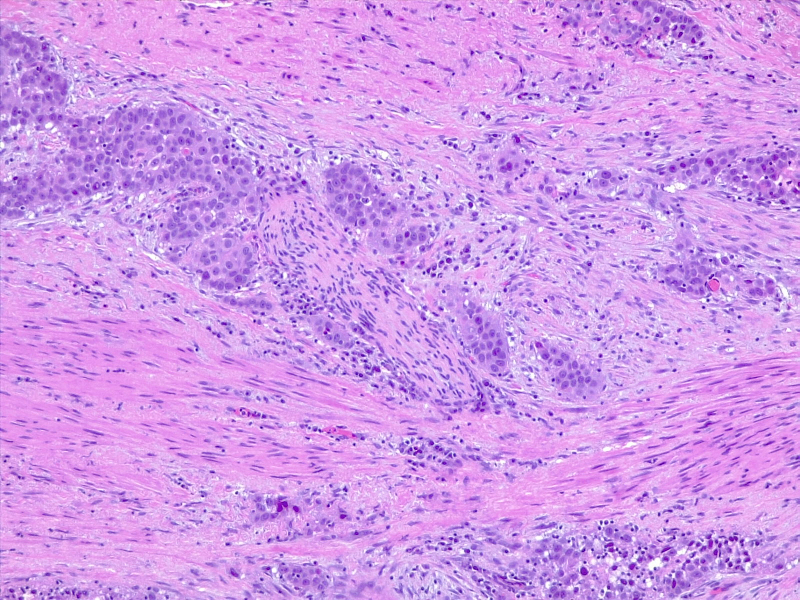

Urothelial carcinoma, perineural invasion

圖4: 尿路上皮癌,神經(jīng)周圍浸潤(rùn)。10x H/E。醫(yī)學(xué)博士 Fabiola Farci 供稿